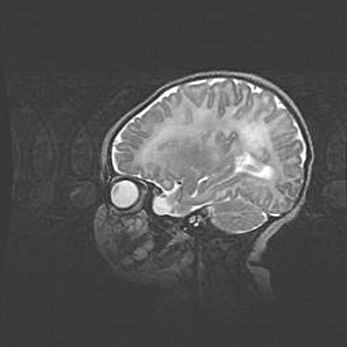

Аномалия Денди-Уокера. Признаки гипоплазии мозолистого тела.

Возраст: 5 месяцев 3 дня

Вес: 5550 г

Пол: мужской

Окружность головы: 39 см

Срок гестации: 40 недель

Аномалия Денди-Уокера – это порок развития головного мозга, для которого характерна триада симптомов: гипотрофия или аплазия червя мозжечка и/или полушарий мозжечка, расширение четвёртого желудочка с формированием ликворной кисты задней черепной ямки, гипертензионная гидроцефалия различной степени.

Гипоплазия мозолистого тела относится к дефектам внутриутробного этапа развития мозговой ткани, возникающим в процессе закладки структур головного мозга, что происходит на начальных этапах развития эмбриона.